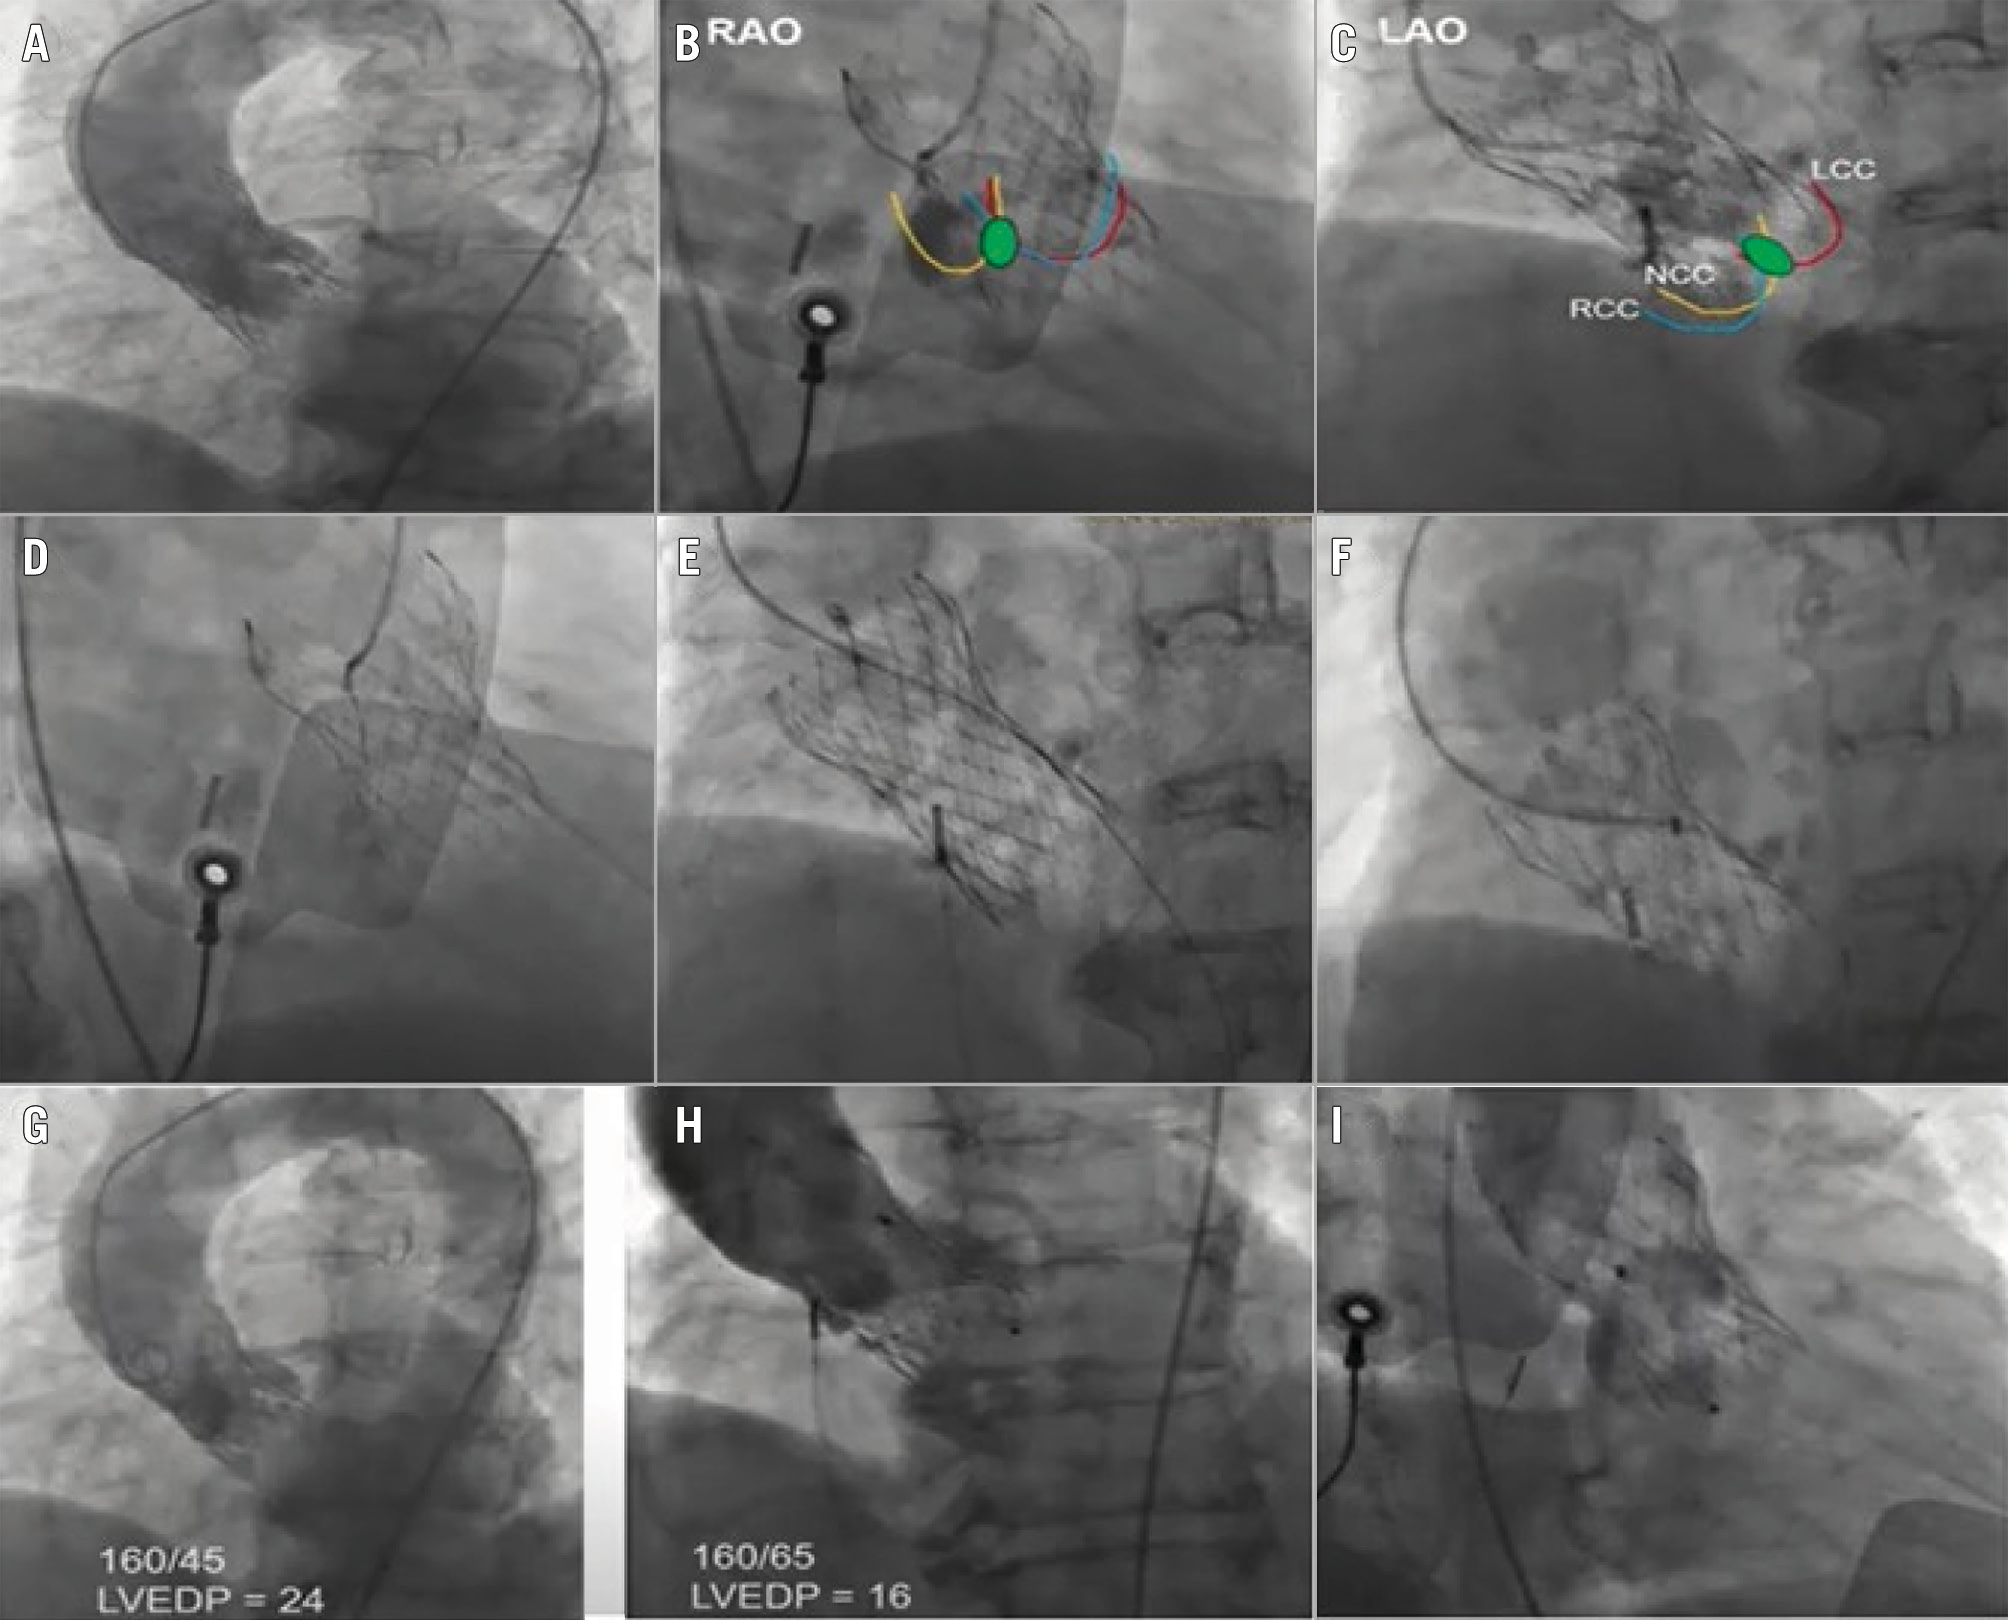

If the paravalvular regurgitation is mild, it can be managed conservatively with periodic follow-up imaging. In patients with moderate-severe or severe PVR, intervention is needed in cases of LV dilatation, heart failure symptoms, or haemolytic anaemia, the latter of which is relatively rare. Surgical aortic valve replacement can be an option; however, the majority of patients with ≥moderate PVR are at high risk for surgery. Transcatheter therapies are often utilised for the management of PVR. The treatment of PVR depends upon the mechanism that is leading to AR. Recognising the main PVR mechanism is therefore critical for choosing the most suitable approach; this can become more complex when there are multiple underlying mechanisms. Irrespective, in the acute setting when a temporising measure is necessary, ventricular pacing at high rates decreases the regurgitant volume. First, PVR can occur due to undersizing of the valve prosthesis. In these cases, balloon dilatation allows for greater valve expansion and reduction of PVL, although it has to be balanced with an increased risk of annular rupture, and hence, caution is required especially in the presence of extensive calcification58. Second, PVR can occur because of suboptimal placement of a prosthesis with incomplete sealing of the annulus by the valve skirt. In these cases, a ViV approach with a second prosthesis can be employed59. Understanding whether the index valve is too high or too low is imperative, as is assurance that coronary flow will be preserved after performing a TAVI-in-TAVI. Third, PVR can occur because of incomplete apposition of the valve stent frame due to calcification of the annulus or native valve leaflets. In these situations, percutaneous paravalvular leak closure plugs can be used60. Figure 6 demonstrates the use of an Amplatzer vascular plug (Abbott) for the management of paravalvular leak in a patient with a prior 29 mm Evolut valve who had symptomatic aortic regurgitation. In a multicentre registry, Landes et al61 reported the outcomes of 201 patients with greater than moderate PVR who underwent redo-TAVI, vascular occluder plug or balloon valvuloplasty: 43% underwent redo-TAVI, 39% underwent placement of a vascular occluder device, and 18% underwent balloon valvuloplasty. There were lower rates of persistent moderate or greater PVR after redo-TAVI than after either of the two other treatment modalities.

Figure 6. Management of paravalvular leak in a symptomatic 77-year-old female with a prior 29 mm (Medtronic) Evolut valve, using an Amplatzer vascular plug (Abbott). A) Aortogram showing moderate to severe aortic regurgitation; (B, C) localisation of the paravalvular leak in the RAO and LAO views; (D) crossing the leak with a stiff, angled Glidewire (Terumo); (E) confirming the crossing; (F) crossing with a Cook Medical sheath and deployment of a 12 mm AVP II; (G) pre- and (H) post-aortogram with improvement in haemodynamics; (I) final aortogram. AVP: Amplatzer vascular plug; LAO: left anterior oblique; LCC: left coronary cusp; LVEDP: left ventricular end-diastolic pressure; NCC: non-coronary cusp; RAO: right anterior oblique; RCC: right coronary cusp